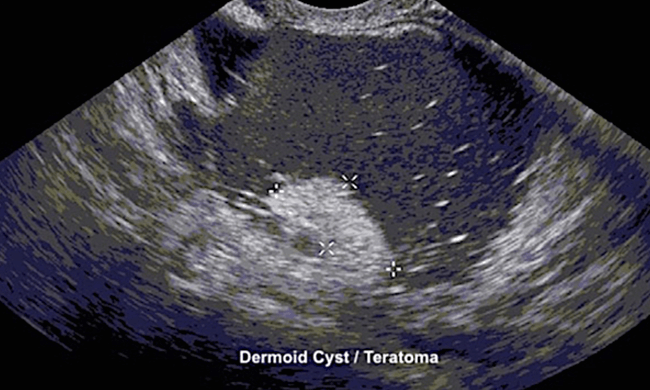

“组织囊肿”或皮样囊肿(或良性成熟囊性畸胎瘤)通常含有油性组织和毛发。皮样囊肿的形成是因为卵巢中的细胞可以发育成任何类型的身体组织。因此,这些囊肿通常含有皮肤、脂肪、骨骼和软骨。10%的情况下,皮样囊肿会发生在双侧卵巢。